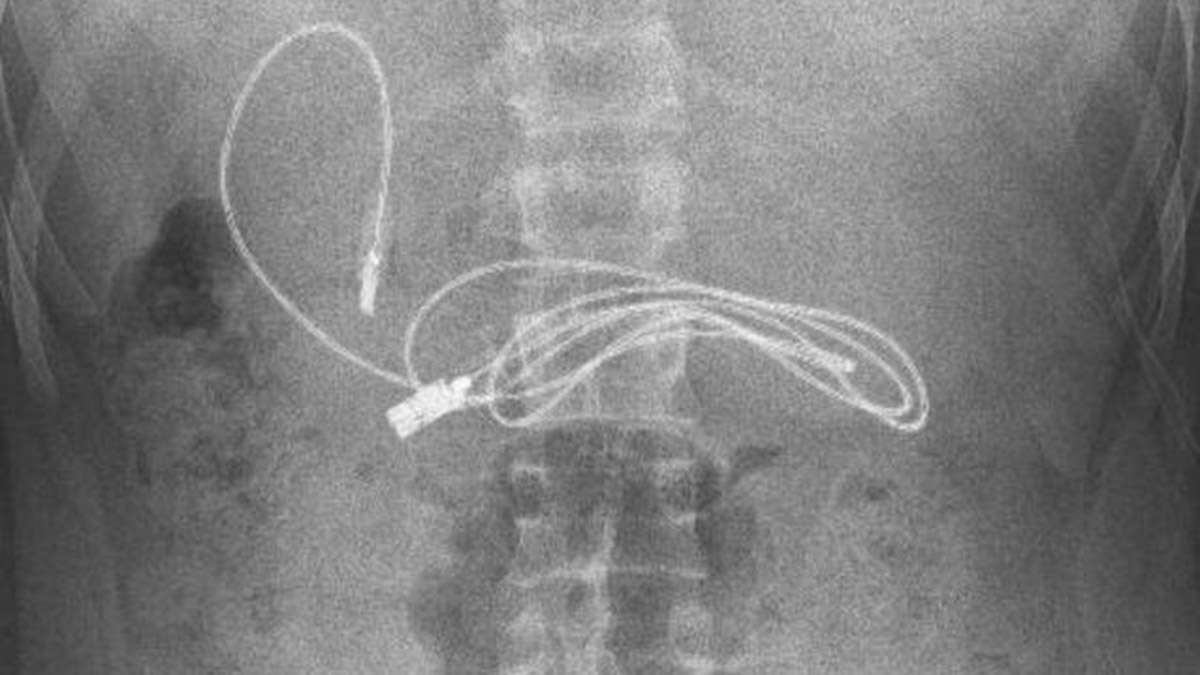

Diyarbakır’da kusma ve bulantı şikayetiyle hastaneye götürülen 15 yaşındaki çocuğun midesinden 1 şarj kablosu ve toka çıktı.

Diyarbakır’da kusma ve bulantı şikayetiyle ailesi tarafından hastaneye götürülen erkek çocuğunun çekilen röntgeninde, midesinde şarj kablosu ve toka olduğu tespit edildi. Bunun üzerine çocuk, ambulans ile Fırat Üniversitesi Hastanesi’ne sevk edildi. Üniversitenin Çocuk Gastroenteroloji Hepatoloji ve Beslenme Bilim Dalı Başkanı Prof. Dr. Yaşar Doğan ve ekibi tarafından yapılan endoskopik işlemle çocuğun midesindeki kablo ve toka başarıyla çıkarıldı. Tedavisinin ardından sağlığına kavuşan çocuk taburcu edildi.

Ameliyatı gerçekleştiren Prof. Dr. Yaşar Doğan, kablonun bir ucunun ince bağırsağa geçmesi nedeniyle zorlandıklarını ifade ederek, “Hastanın kusma ve karın ağrısı şikayetleri olması üzerine sağlık kuruluşuna başvurulmuş. Orada yapılan incelemelerde hastanın midesinde kablo tespit edilmesi üzerine bize danışıldı. 112 aracılığıyla hastaya gerekli işlemi yapıp yapmayacaklarını bize sordular. Biz de hastayı bize gönderebileceklerini kendilerine ilettik. Hasta bize geldikten sonra ön hazırlık yapıldı ve gerekli olan açlık süresinin ardından hastaya endoskopik işlem yapıldı. Endoskopik işlemle midedeki kablo çıkarıldı. Kabloyu çıkarırken açıkçası zorlandık, çünkü kablonun bir ucu ince bağırsağa geçmişti. İşlem başarılı bir şekilde sonlandırıldıktan sonra hasta sağlıklı bir şekilde evine gönderildi” dedi.